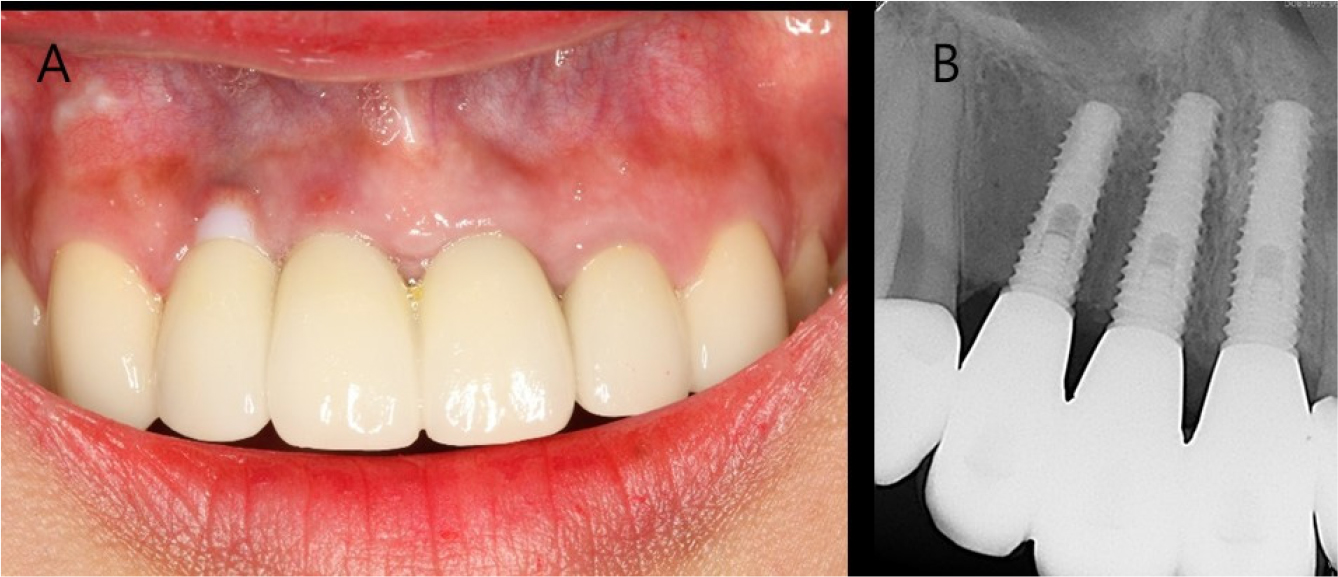

A 26-year-old woman complained of gingival recession around a maxillary anterior implant restoration. The patient had a splinted restoration with 3 implants in the maxillary anterior region placed immediately after tooth extraction (#12, #11, and #21) because of root fracture 2 years before. Bone or soft tissue grafting was not performed according to the patient interview. Clinical examination revealed gingival recession around the implant restoration in the right maxillary lateral incisor region, exposed zirconia abutment, and a gray fixture below the gingiva. A deep periodontal pocket and thin periodontal biotype were observed on the buccal side (Fig. 1).